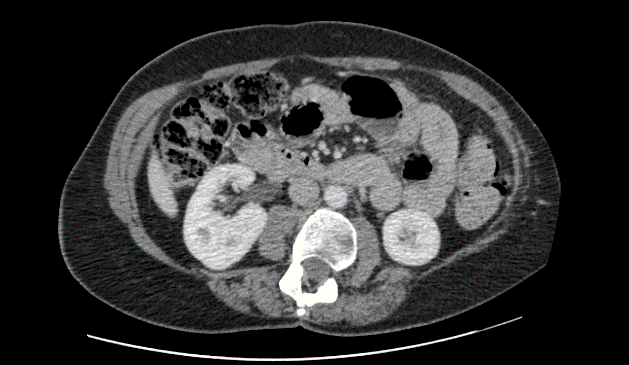

At 15 months post-op examination of the repair site and CT of the abdomen revealed no evidence of seroma or recurrent hernia (Figure 5). The patient was reporting a degree of pain at the repair site. At 18 months post-operation, eight Ethibond® (Ethicon) transfascial sutures were removed under general anaesthetic as a day case, which relieved the majority of her symptoms. Further follow up of the patient (to 34 months post-op) has shown no clinical or radiological hernia recurrence (Figure 6).

Figure 5: CT scan transverse image performed 15 months post-operation.